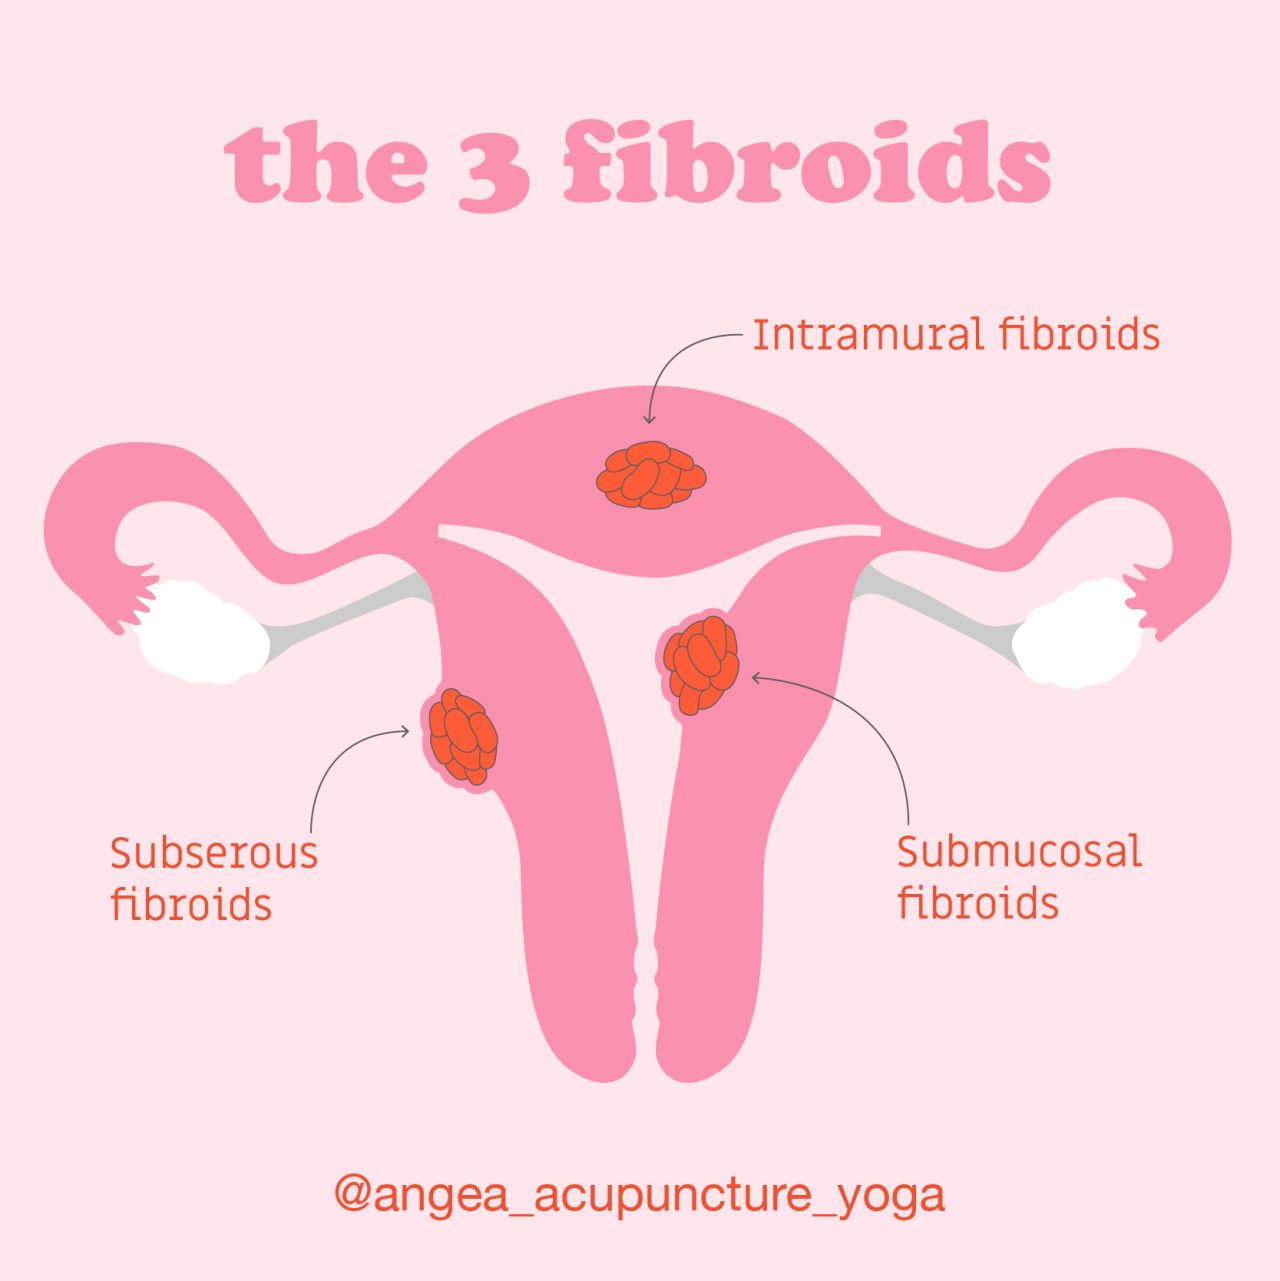

What Are Fibroids? – Angea

What are the Symptoms of Fibroids? – Best Acupuncture Hamilton NZ

Types of Fibroid’s? | Fibroids, Hospital, Intramural

What Causes Fibroids? – Best Acupuncture Hamilton NZ

Uterine Fibroids – Best Acupuncture Hamilton NZ